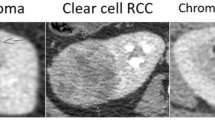

Solid renal masses (SRM) are difficult to differentiate based on standard MR features. The purpose of this study was to assess MR imaging features of SRM to evaluate performance of ensemble methods of classifying SRM subtypes.

In the test dataset, GBM and RF models demonstrated an accuracy of 86% (95% CI 75% to 93%) for predicting benign versus malignant SRM compared to 83% (95% CI 71% to 91%) for the RP model. RF had the greatest accuracy in predicting SRM subtypes, 81.2% (95% CI 69.5% to 89.9%) compared with GBM 73.4% (95% CI 60.9% to 83.7%) or RP 70.3% (95% CI 57.6% to 81.1%). Marginal homogeneity was reduced by the RF model compared with the RP model (P < 0.001), but not the GBM model (P = 0.135). All models had high sensitivity and specificity for clear cell and papillary renal cell carcinomas (RCC), but performed less well in differentiating chromophobe RCC, oncocytomas, and fat-poor angiomyolipomas.

Ensemble methods for prediction of SRM from radiologist-assessed image characteristics have high accuracy for distinguishing benign and malignant lesions. SRM subtype classification is limited by the ability to categorize chromophobe RCCs, oncocytomas, and fat-poor angiomyolipomas.